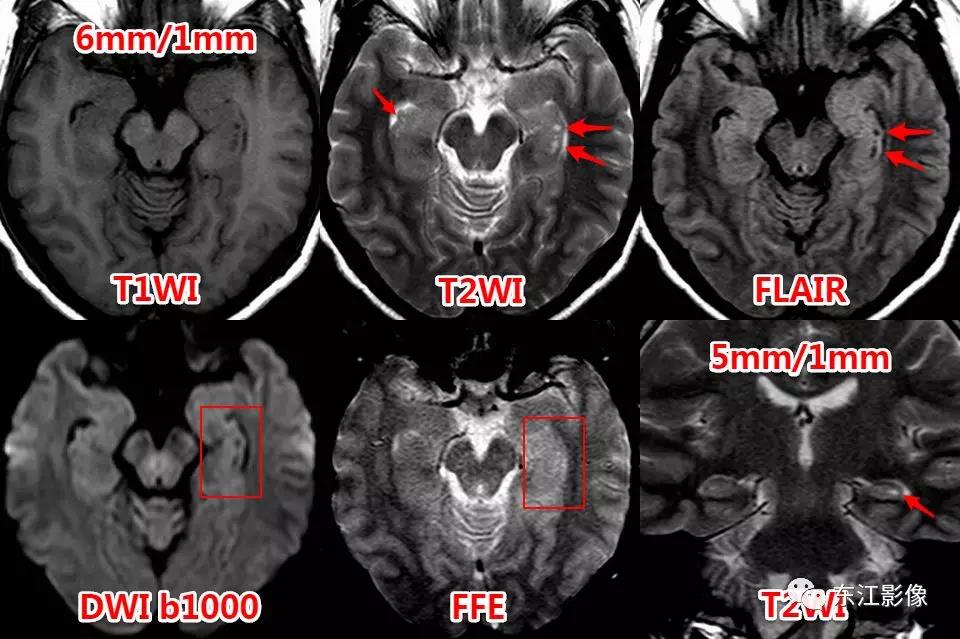

海马沟残余囊肿

海马沟残余囊肿是常见的正常变异,影像学表现为串状分布的小的脑脊液样“囊肿”,位于海马区域,紧邻侧脑室颞角内侧。

一般是由于胚胎期海马角和齿状回的缺陷或不完全融合所致,不引起临床症状。

由于MRI的广泛应用,检出率非常高,尤其是薄层图像。

不熟悉的话,容易被误认为腔隙灶或囊肿。

图1 海马沟残余囊肿